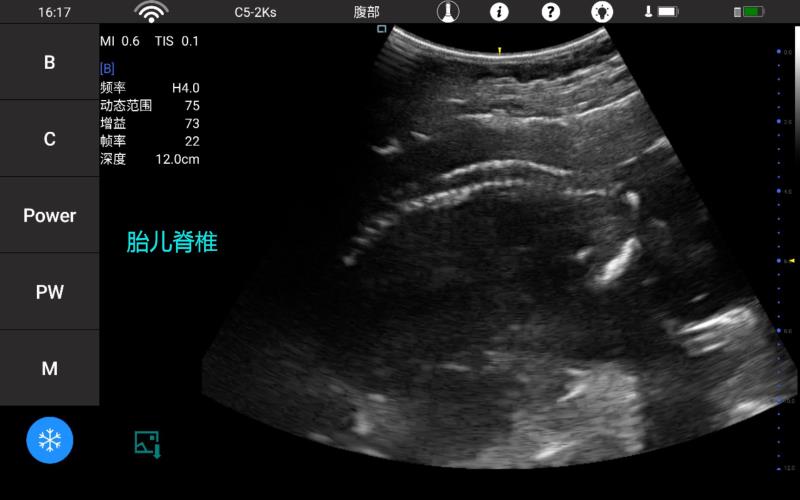

• 微凸

腹部

肾脏

新生儿颅脑

及心脏

小动物等

• 大凸

妇科产科

心脏

肺等